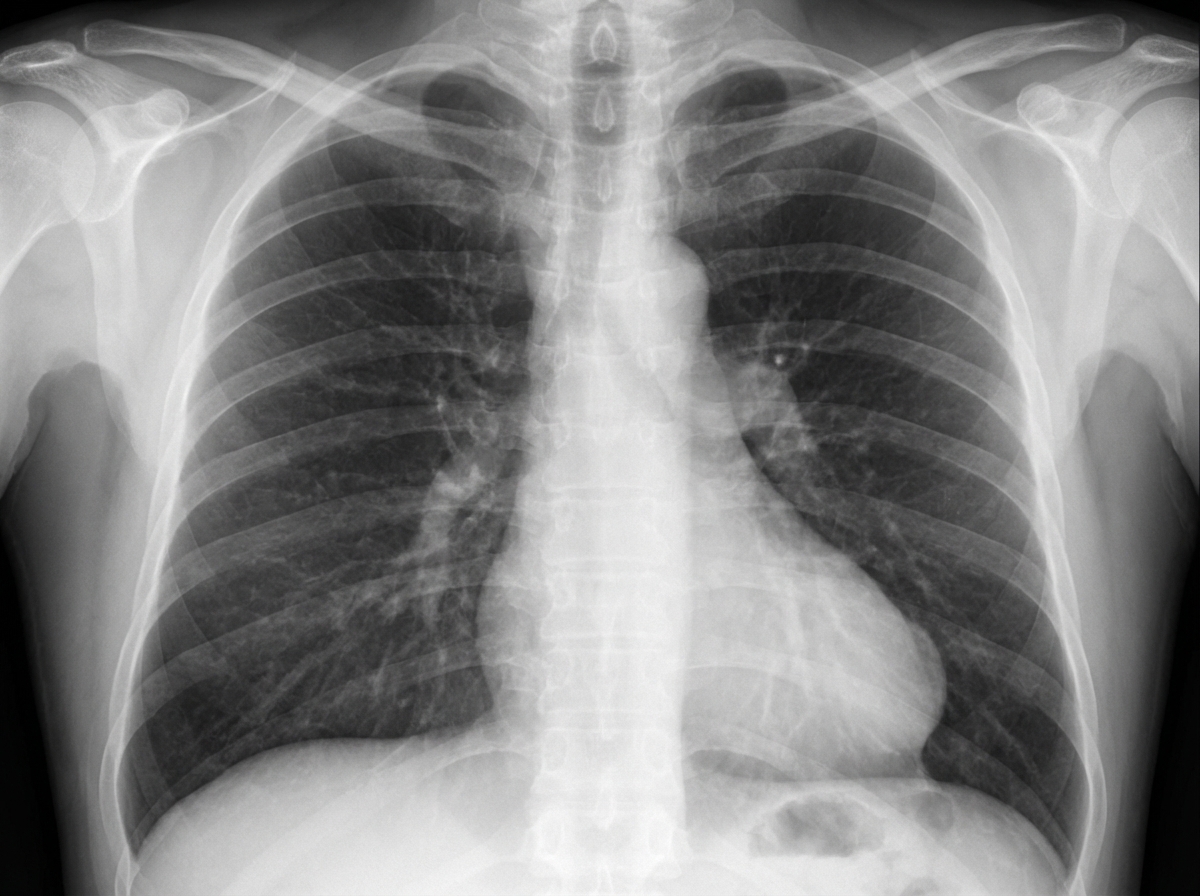

A 67-year-old male smoker presents with cough and was treated for acute bronchitis. A chest X-ray prompted a referral to the chest clinic. The patient has a past history of myocardial infarction but is currently asymptomatic. Blood pressure is 128/80, and cardiopulmonary examination is unremarkable. A purified protein derivative (PPD) test result is 7 mm. The chest X-ray is shown. What is the likely diagnosis?

Explanation: ***Left ventricular aneurysm*** - In a patient with **previous myocardial infarction**, a localized bulge at the **left cardiac border** on chest X-ray is characteristic of a **left ventricular aneurysm** formation. - The **asymptomatic presentation** with normal cardiopulmonary examination is typical, as many LV aneurysms remain clinically silent until complications develop. *Hypertensive cardiomyopathy* - Would present with **generalized cardiomegaly** rather than a localized cardiac border bulge seen on the chest X-ray. - The patient's **normal blood pressure** (128/80) makes active hypertensive heart disease unlikely. *Tuberculous pericarditis* - A **PPD test of 7 mm** is considered **negative** in immunocompetent individuals, making active tuberculosis unlikely. - Would typically present with **pericardial effusion** causing a globular heart shadow, not a localized bulge. *Epicardial fat pad* - Appears as a **smooth, well-defined opacity** at the **cardiophrenic angles**, not as a bulge at the left cardiac border. - More commonly seen in **obese patients** and would not be related to the patient's **history of myocardial infarction**.